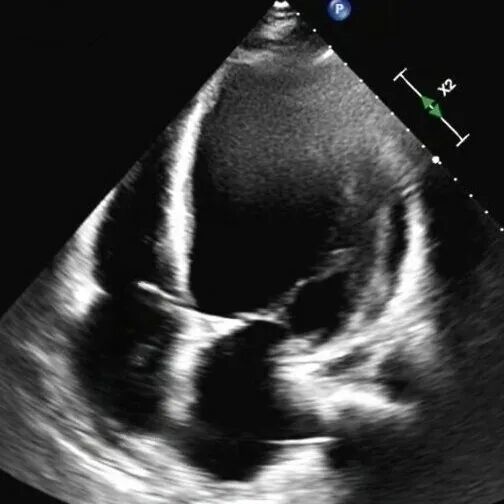

61岁的李先生(化名)三年前就偶尔出现胸闷乏力,一个月前,他因夜间无法平卧、呼吸极度困难,被紧急送往beat365中文官方网站第一附属医院(第一临床医学院)心脏重症监护室。通过系统检查,李先生左室舒张末期内径102mm(男性的正常值≤55mm),主动脉根部瘤样扩张63mm(正常≤35mm),左室射血分数仅21.83%(正常≥50%),心功能IV级(NYHA分级),主动脉瓣重度关闭不全,二尖瓣轻-中度关闭不全,最终确诊为终末期心衰,巨大心脏,主动脉根部瘤样扩张,随时发生主动脉夹层/主动脉破裂危及生命,此外主动脉瓣重度关闭不严,心功能极差,心脏随时可能“停摆”。

术前心脏超声